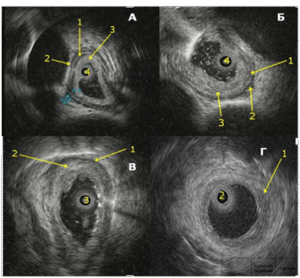

Digital Formats: During EUS, damaged esophageal wall layers were highly echogenic with a heterogeneous echo structure. Increased thickness and impaired differentiation of the contours and boundaries of the damaged esophageal wall layers were noted. Based on changes in their structure during EUS, we developed the following grading for damage to the muscular layers of the esophageal wall: grade 4a, 4b, 4c, 4d (Fig. 1 and Fig. 2).

Fig 1:

Fig 2. A – Grade 4a esophageal reflux disease. 1 – Impaired differentiation of the mucosa and submucosal layers, 2 and 3 – thickened circular and longitudinal muscle layers, 4 – ultrasound mini-transducer.

B – Grade 4b esophageal reflux disease. 1 – Partially damaged circular muscle layer, 2 – intact longitudinal muscle layer, 3 – damage extending to the submucosal and circular muscle layers, 4 – ultrasound mini-transducer.

B – Grade 4c esophageal reflux disease. 1 – Partially damaged longitudinal muscle layer, 2 – damage extending to the submucosal, circular muscle, and partially longitudinal muscle layers, 3 – ultrasound mini-transducer.

D – Grade 4d esophageal reflux disease. 1 – damage extending to all layers of the esophageal wall, 2 – ultrasound mini-transducer.